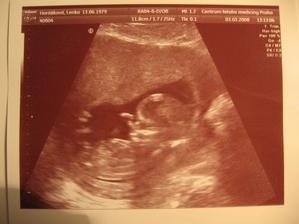

•••••••••• 3.3.2008 jsme byli na NT screeningu, bohužel nám vyšla pravděpodobnost na downův syndrom 1:244, tak nám doporučili odběr z placenty (odběr choriových klků). Jdeme na něj zítra. Jako útěchu, jsme si nechali vytisknout alespoň fotečku našeho ušáčka, jak si cucá paleček. :o)